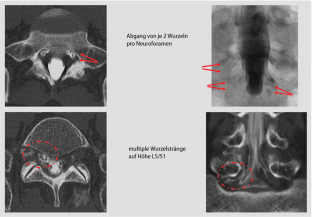

Abb. 3